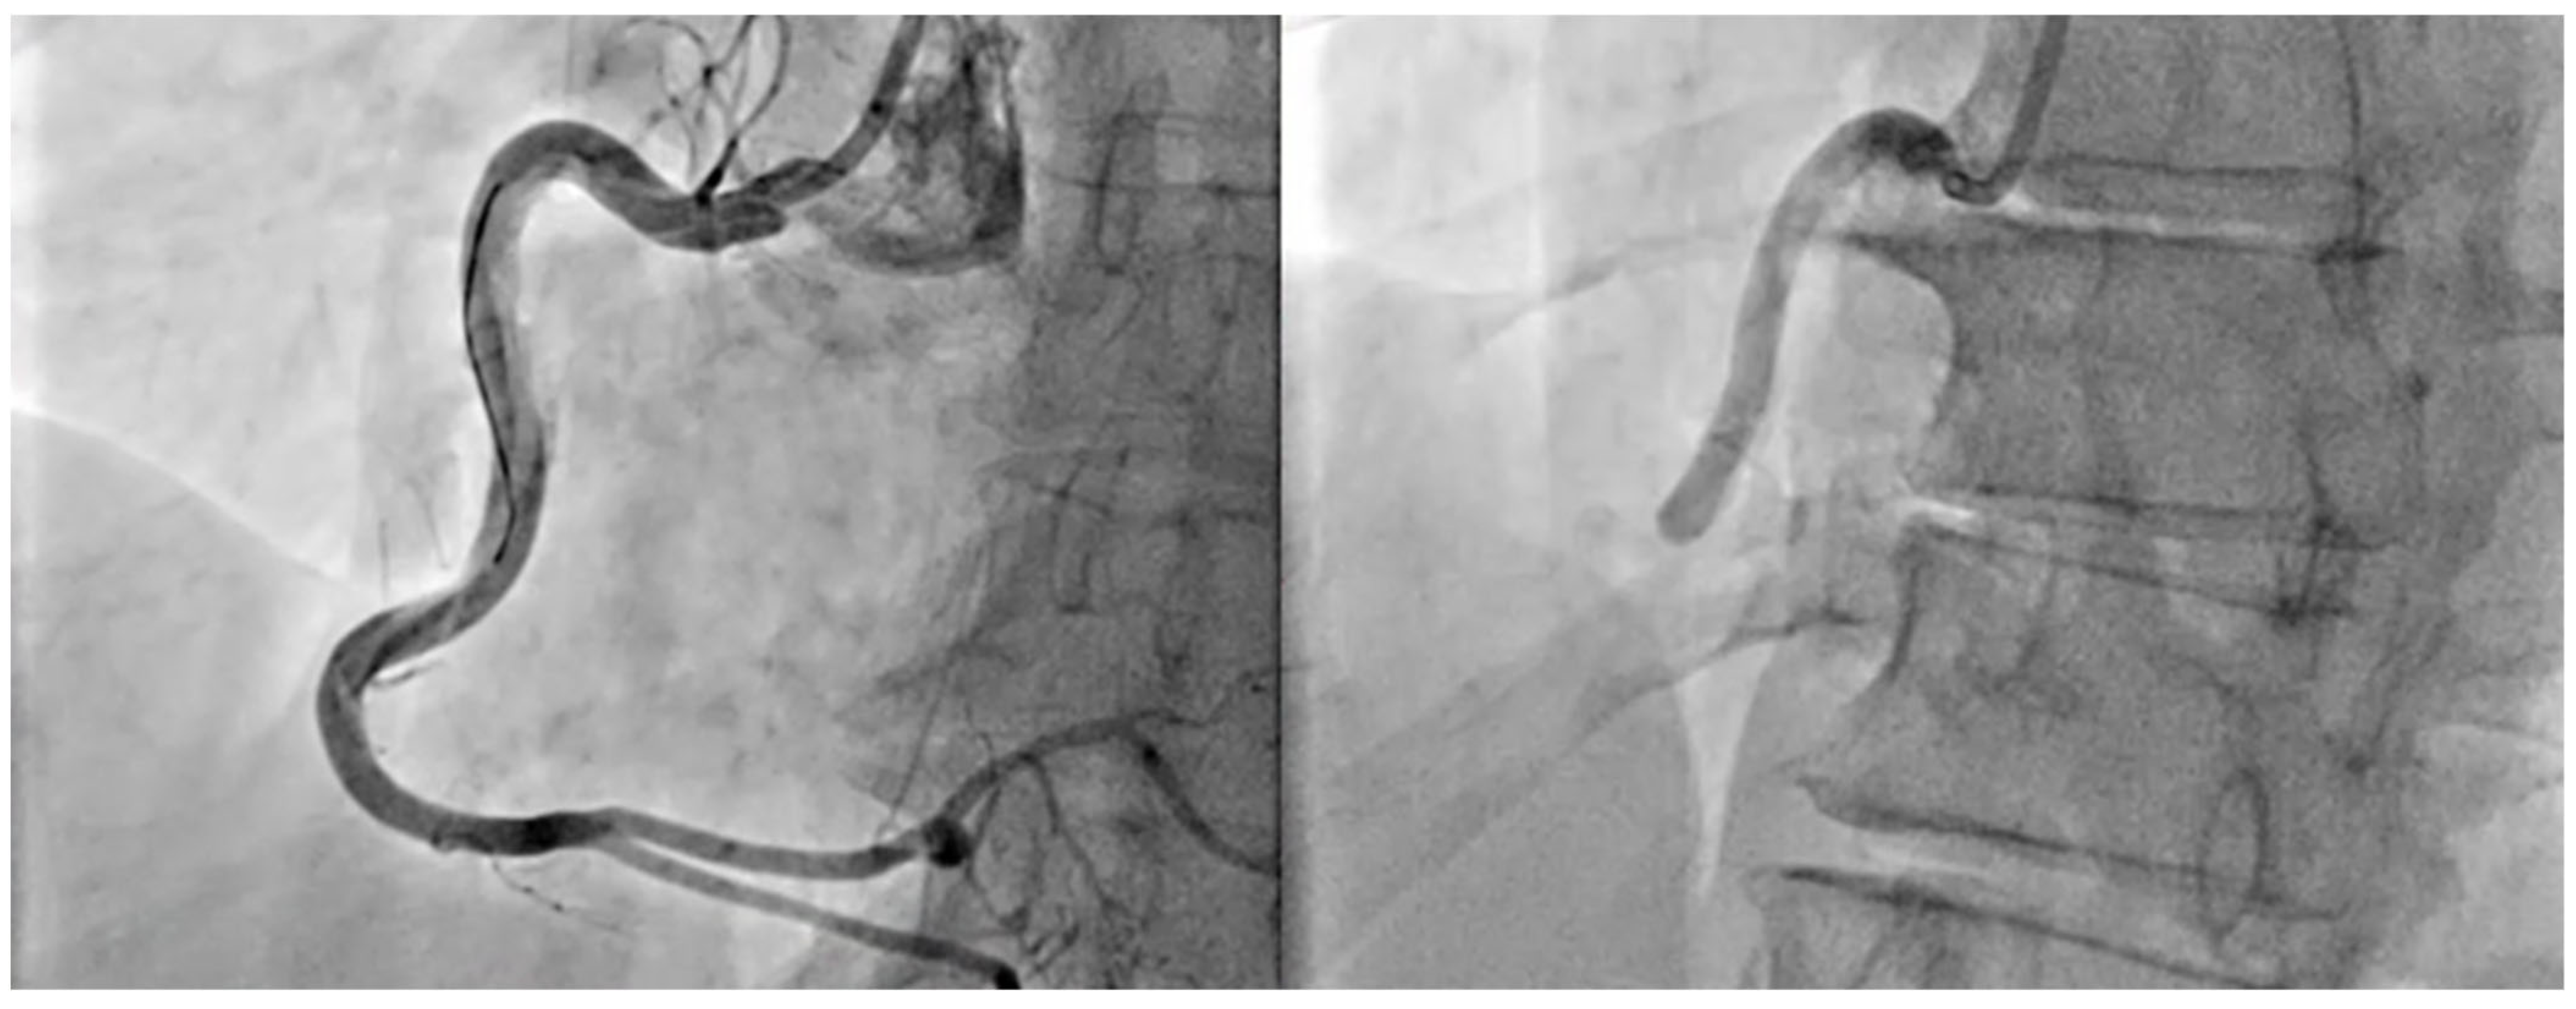

- STEMI (ST-Segment Elevation Myocardial Infarction): Defined by persistent ST-segment elevation on the ECG, typically indicating complete blockage of a coronary artery (Figure 2).

4.1. Treatment of Acute Coronary Syndrome